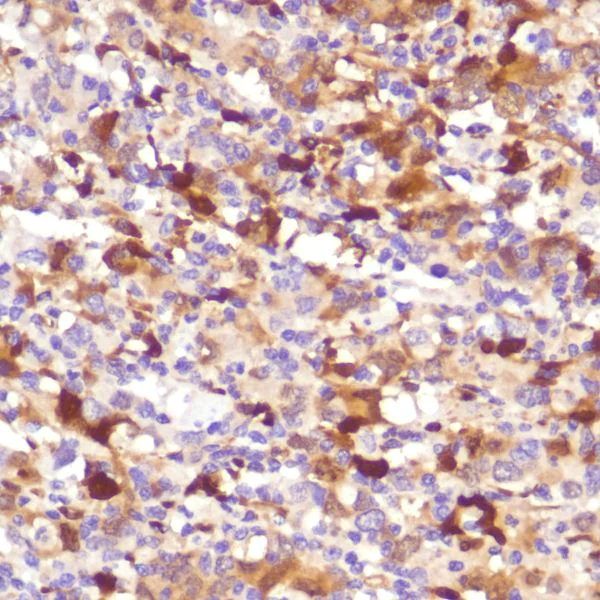

Immunohistochemistry (Formalin/PFA-fixed paraffin-embedded sections) - Anti-Indoleamine 2, 3-dioxygenase antibody [SP260] - C-terminal (AB228468)

Formalin-fixed paraffin-embedded human endometrial adenocarcinoma tissue stained for Indoleamine 2 3-dioxygenase with ab228468 at 1/100 dilution in immunohistochemical analysis.